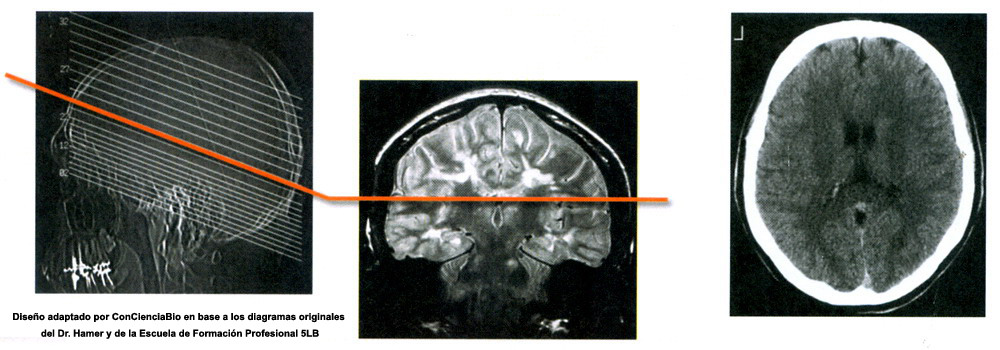

Costellazioni del midollo cerebrale

Condizioni per questa costellazione

Si avrà una costellazione del midollo cerebrale, quando la persona ha almeno due SBS (uno in ognuno dei due emisferi nella sostanza bianca) che siano in una qualsiasi delle seguenti condizioni:- Entrambi gli SBS in fase attiva

- Un SBS in fase attiva e l'altro in PCL

- Un SBS in fase attiva e l'altro in crisi epilettoide

- Entrambi gli SBS in fase PCL

- Entrambi gli SBS in crisi epilettoide

La costellazione del Midollo Cerebrale implica un conflitto attivo di svalutazione nei due emisferi cerebrali, ad esempio: le due ginocchia. La lateralità deve essere presa in considerazione.